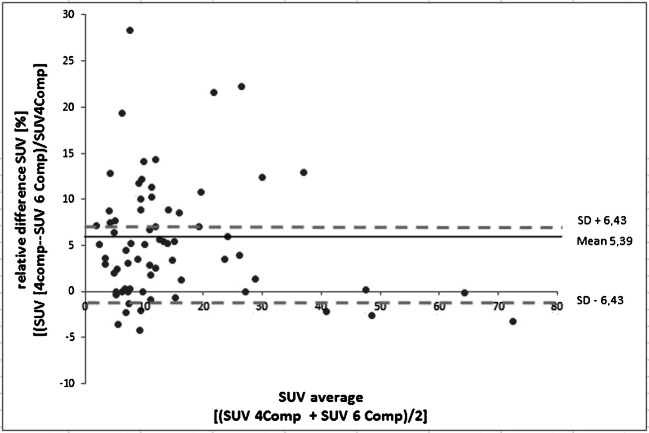

Overall, 69 bone lesions were detected in all PET data reconstructions using three different AC methods for each patient examination. The Bland−Altman plot in Fig. 2 shows the relative differences between the standard 4-compartment and improved 6-compartment AC in the measured SUVmax of the 69 detected lesions. Note the overall gain in SUVmax due to the 6-compartment AC including bone and HUGE information. Considering all 69 lesions, the mean increase in SUVmax is 5.4 ± 6.4%. The total range was − 4.3% up to 28.4%. Maximal relative differences occurred in lesions close to bone or truncations.

Fig. 2.

Bland–Altman plot shows the relative quantitative impact of the 6-compartment AC on SUVmax in 69 detected bone lesions when compared with the 4-compartment AC serving as reference. The mean increase in SUVmax of all 69 lesions is 5.4 ± 6.4%. The total range is − 4.3% up to 28.4% in individual lesions close to bone or truncations

Table 2 lists examples of six lesions that showed the highest quantitative impact on SUVmax due to application of improved AC. The highest relative increase in SUVmax with 28.4% could be observed in the thoracic spine (lesion no. 4). The second highest relative increase in SUVmax with 22.3% was observed in the os sacrum (lesion no. 3) of one patient. In these two examples, the relative impact of HUGE truncation correction on lesion SUVmax was higher than the relative impact of adding bone information (diff. 4-comp. vs. 5-comp.) to the μ-map. For the remaining four specific lesion examples, the relative quantitative impact of adding bone was higher than the relative impact of HUGE truncation correction.